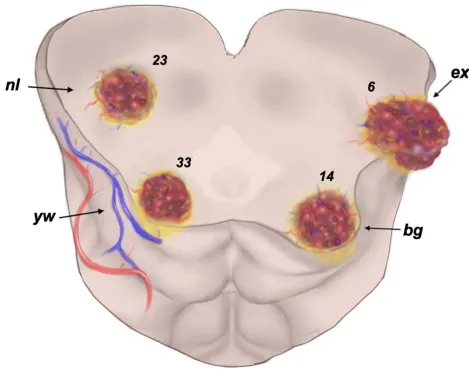

研究团队回顾分析25年间接受显微手术的76例中脑海绵状血管瘤患者,创新性根据病变与脑干表面关系,将中脑海绵状血管瘤分为4种类型(基于病变外在表现):

nl型:病变位于中脑深部,表面完全正常(占30.3%);

yw型:表面仅见含铁血黄素沉积导致的黄色改变(占43.4%);

bg型:病变位置较浅,导致中脑表面隆起,但表面仍有薄层脑实质覆盖(占18.4%);

ex型:病变已突破脑表面,直接可见(占7.9%)。

常规认知可能认为nl型(深部、表面正常)手术难度最大、预后最差。但数据显示:nl型患者术前平均mRS评分(评估神经功能,0分正常,5分卧床)为1.43,术后随访降至0.61;恢复效果甚至优于bg型(表面隆起)和ex型(外生),且全组76例患者无手术死亡病例。

换言之,病变“深在”并不代表手术风险高或恢复差。只要能够精准定位病变、操作轻柔,深部中脑海绵状血管瘤患者同样可获得良好神经功能恢复。